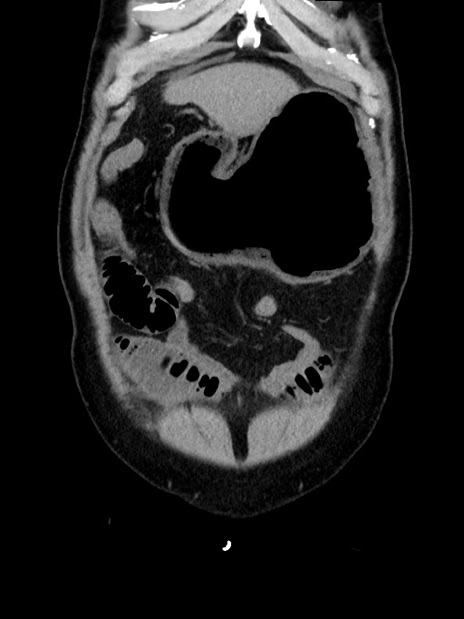

症例35(冠状断像)

【症例】70歳代 男性

【主訴】腹部膨満、嘔吐

【現病歴】昨日より腹部膨満感出現。本日増悪し、仙痛出現。嘔吐あり、受診。

【既往歴】糖尿病、胆摘後

【身体所見】BP 149/80mmHg、HR 74/min、BT 35.9℃、腹部:膨満、軟、圧痛なし。腸雑音減弱あり。上腹部正中切開瘢痕あり。

【データ】WBC 13500、CRP 1.72